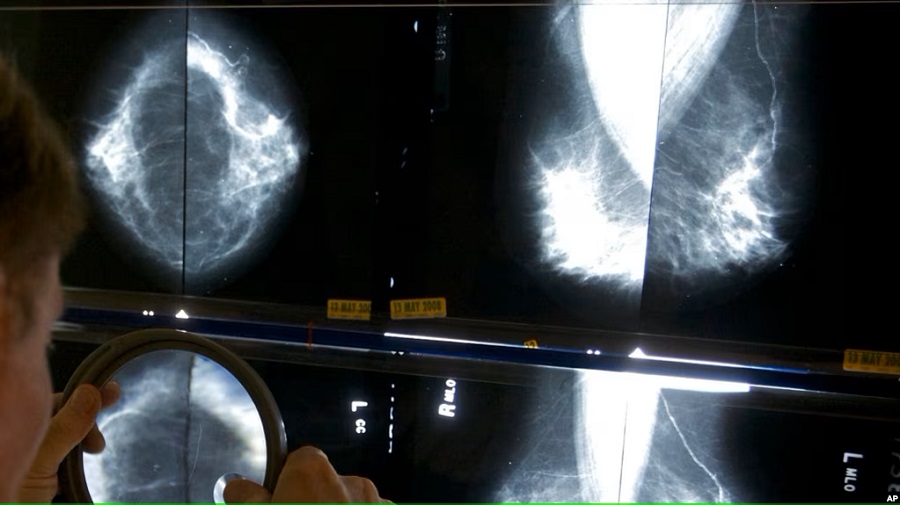

Washington Radiology es uno de varios centros que ofrecen este tipo de pruebas en todo el país. Aunque las radiografías de mama generalmente se utilizan para detectar y diagnosticar cáncer, las imágenes también indican si las arterias de los senos tienen calcificaciones, que en la imagen aparecen como líneas blancas paralelas.

Las calcificaciones, que se consideran hallazgos “incidentales” no relacionados con el cáncer de mama, pueden estar asociadas con el riesgo de enfermedad cardíaca de una persona.

Estas calcificaciones han sido visibles en las imágenes durante décadas y algunos radiólogos las han anotado rutinariamente en sus informes. Sin embargo, no se solía dar esta información a los pacientes.